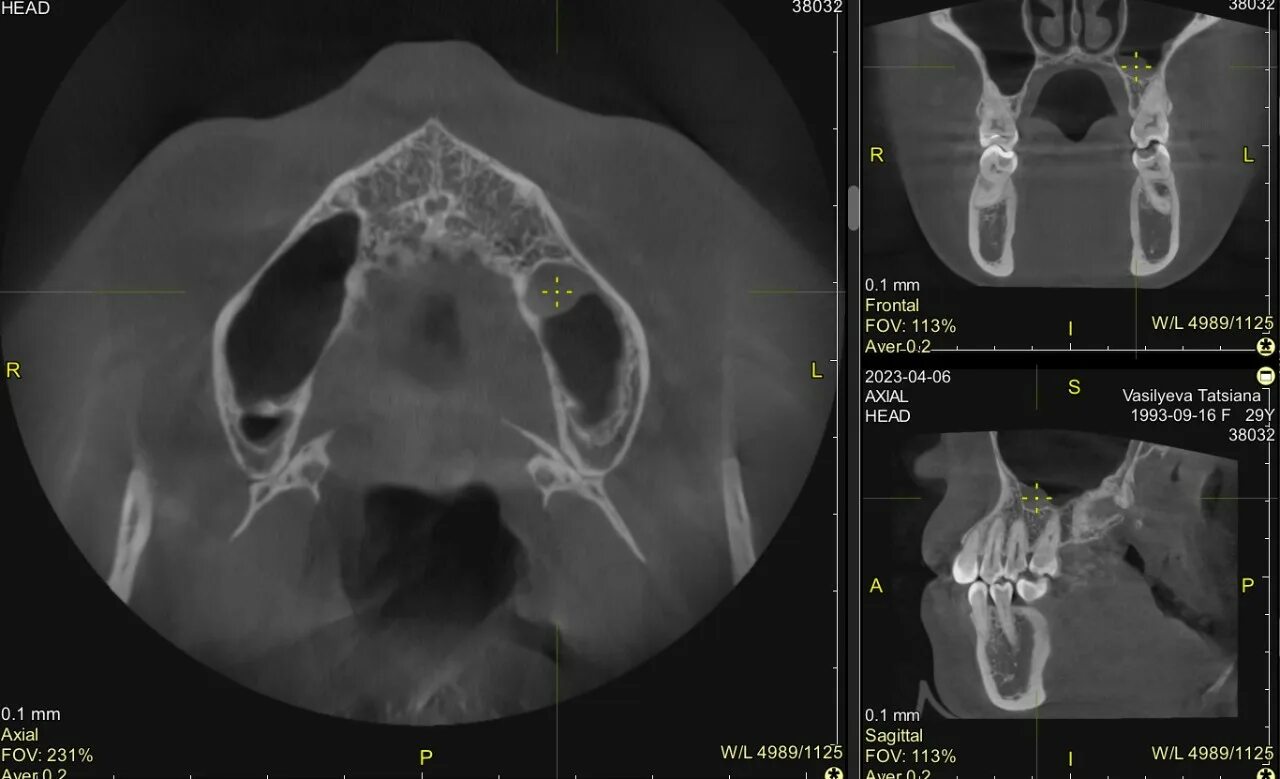

Как лечить утолщение слизистой верхнечелюстной пазухи